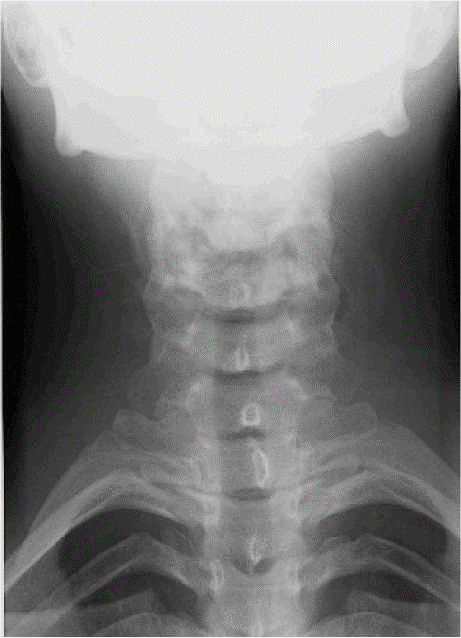

IMAGE NORMALE

RAYON DIRECTEUR

– – Il est ascendant de 15 à 20° en fonction de la lordose

– – Il est centré sur C6

VARIANTE

– – En postéro-antérieur, avec un rayon directeur ascendant

– – En décubitus dorsal